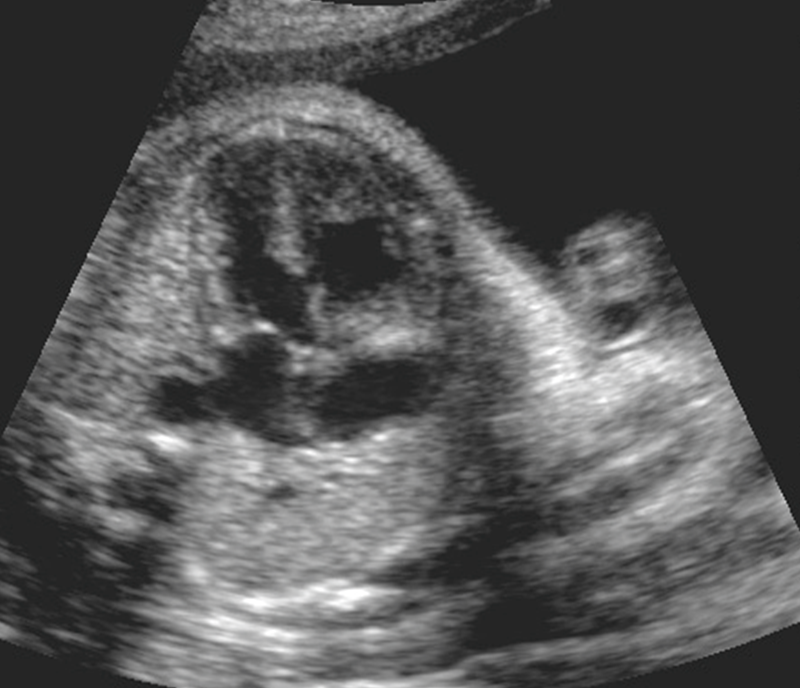

What is the seen with a complete AVSD?

Single large AV valve stretching across both of the ventricles

Systole AVSD [different sizes of atrium]

Diastole AVSD